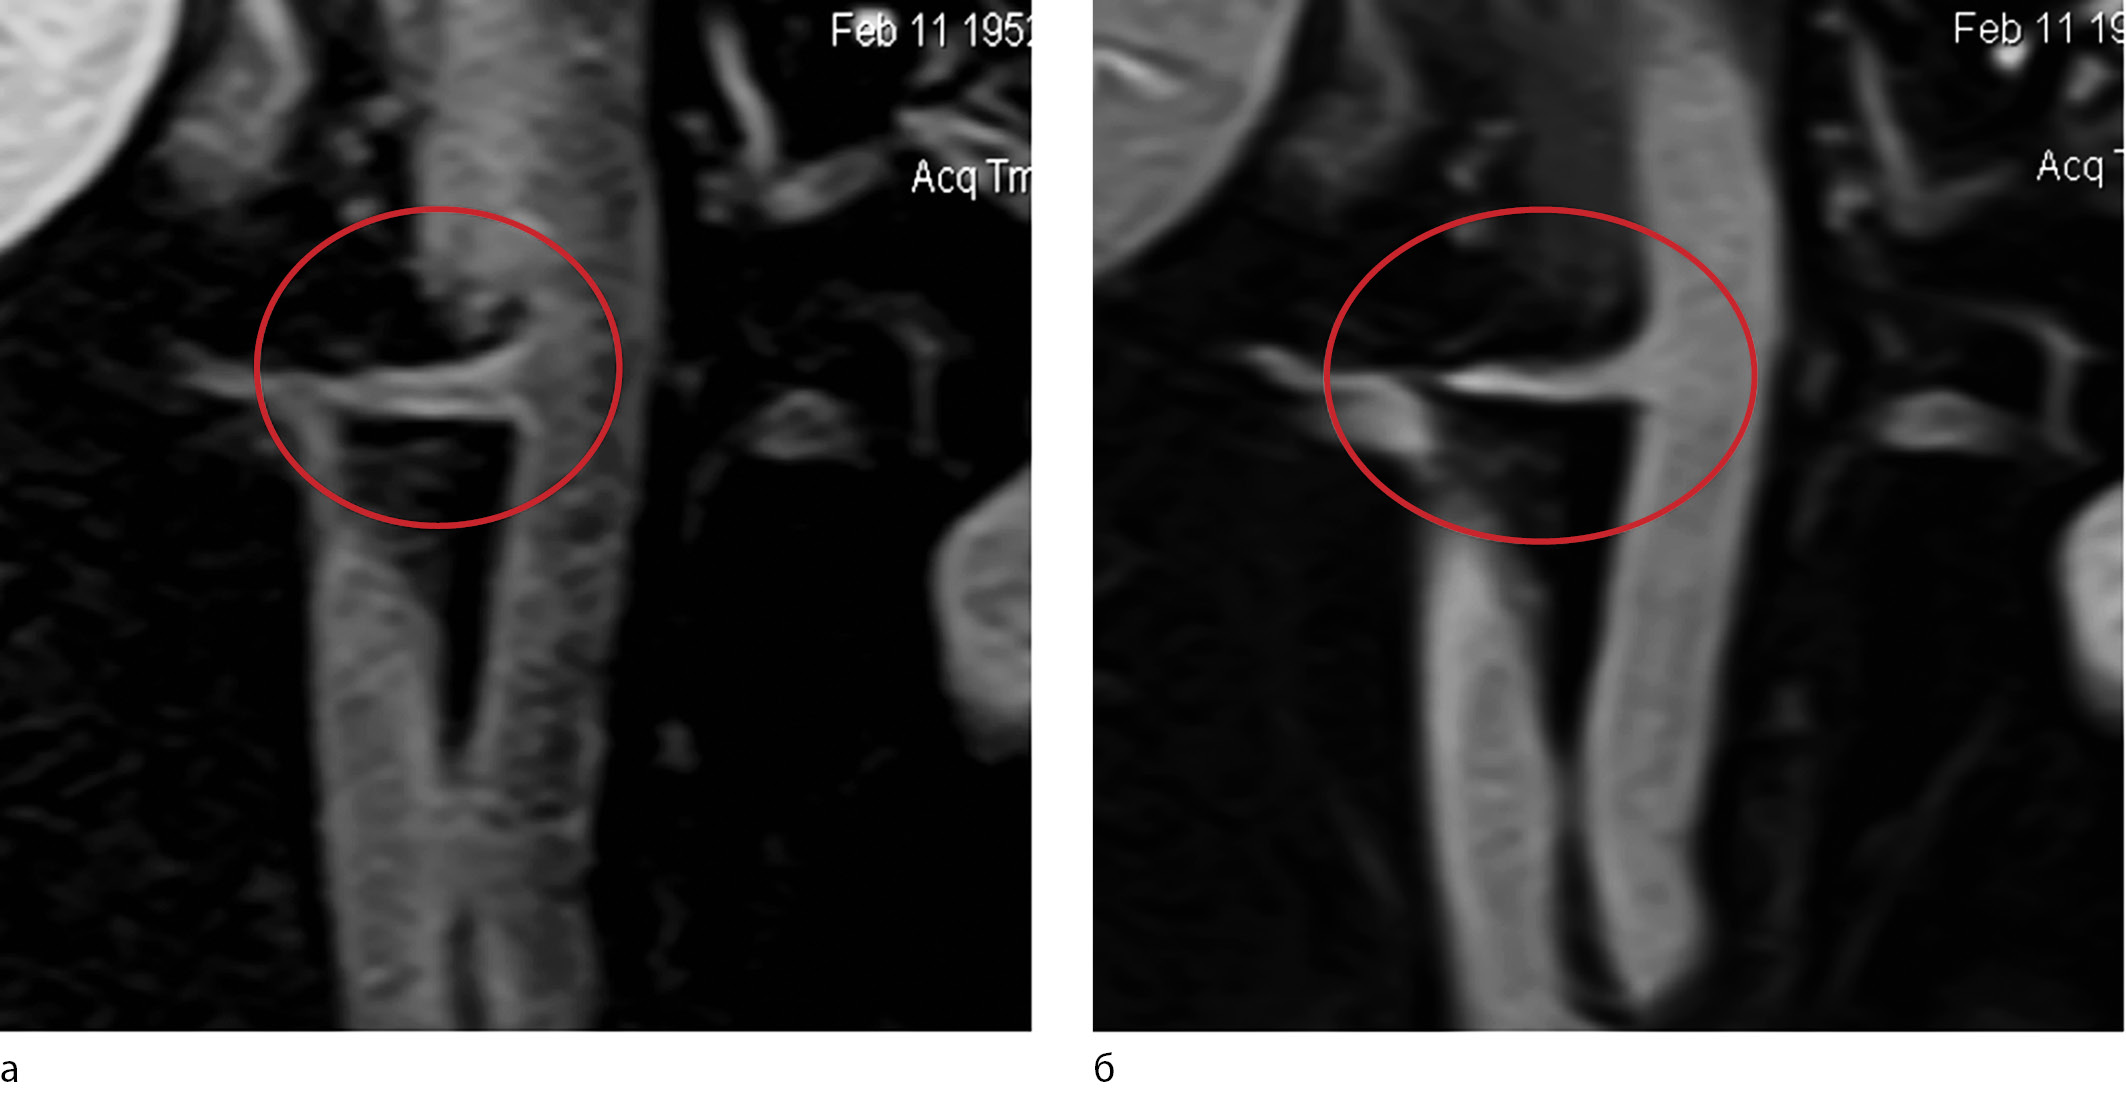

The accumulation of contrast agent in the wall of the RAs was analysed as follows. At the workstation, the software determined the intensity of the magnetic resonance imaging (MRI) signal from the artery wall in T1-weighted spin-echo (SE) images before and after the administration of the contrast agent. The MRI image of the enhancement of the MR signal from the walls of the RAs is presented in Fig. 1. Then, the enhancement index (EI) of the MRI signal was calculated as the ratio of the post-contrast T1 image to the original one:

Fig. 1. Magnetic resonance imaging of the abdominal aorta and renal arteries extending from it in a coronary projection on a T1-weighted spin-echo image (a) before and (b) after the contrasting. The area of interest – the trunk of the right renal artery with clearly visible walls – is highlighted [30].

1. Fig. 1. Magnetic resonance imaging of the abdominal aorta and renal arteries extending from it in a coronary projection on a T1-weighted spin echo image before (a) and after (b) contrast. An area of interest was identified - the trunk of the right renal artery with clearly visible walls [30]. | |